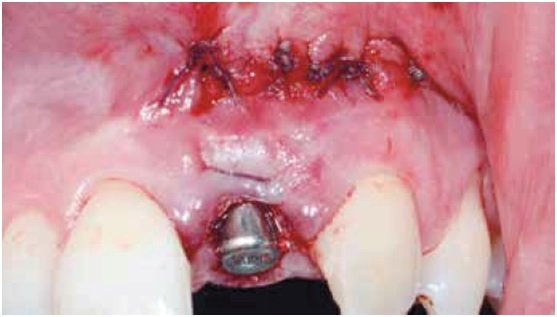

O tratamento consistiu na extração atraumática do dente e incisão de acesso na região periapical, para facilitar o procedimento de debridamento e minimizar o trauma mecânico na região cervical. Após remoção superficial do osso infectado e curetagem da região, um implante foi imediatamente instalado e a região apical foi preenchida com hidroxiapatita sintética para recuperar o volume perdido. No mesmo dia, uma provisória apoiada nos dentes adjacentes foi instalada e, após cinco meses, o paciente recebeu tratamento protético definitivo. Considerações sobre aspectos teóricos e práticos do procedimento são apresentadas e discutidas, com ênfase na previsibilidade estética do tratamento.